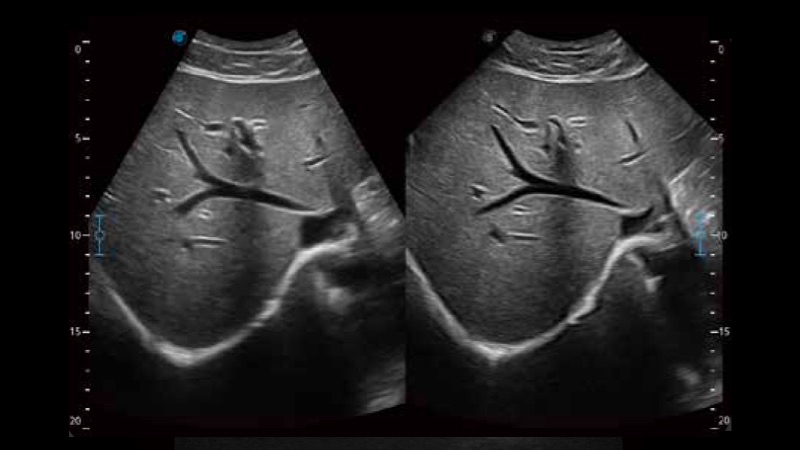

開立醫(yī)療通過不斷的技術(shù)創(chuàng)新,為大眾的生命健康提供持續(xù)關(guān)愛。P12 Plus采用全新一代超聲成像平臺,新平臺旨在將真實(shí)還原組織解剖結(jié)構(gòu)作為首要目標(biāo)。平臺采用全新集成化硬件模塊,搭載新一代芯片,系統(tǒng)性能得到大幅提升,為您的診斷提供了豐富的臨床信息。優(yōu)異的圖像表現(xiàn),豐富的探頭配置,全面的應(yīng)用功能,為您日常診斷提供了可靠的助手。

彩色多普勒超聲診斷系統(tǒng)